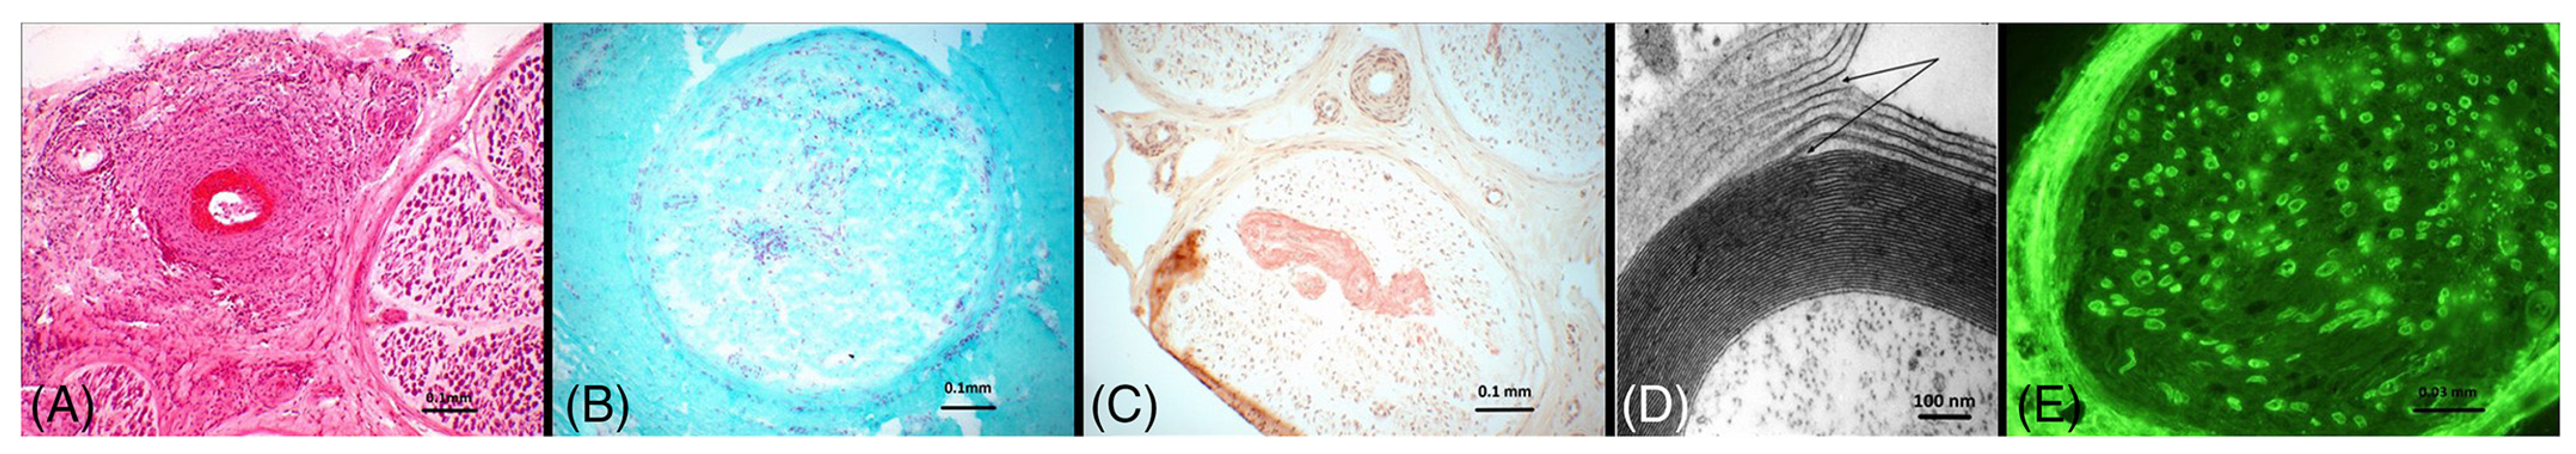

2.3.1. Chronic Inflammatory Demyelinating Polyneuropathy (CIDP)

2.3.2. Paraproteinemic Neuropathy